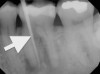

Chronic apical abscess is typically indicated by a radiograph that reveals a radiolucency. Clinically, there is a sinus tract present on the gingival tissue. It is paramount that the draining sinus tract be traced with a gutta-percha cone and then radiographed (Figure 3 and Figure 4).

Clinical confirmation of the periradicular diagnosis—chronic apical abscess on tooth No. 19. The tooth is not sensitive to percussion or palpation. A gutta-percha #25/.04 cone is inserted into the sinus tract.

Radiographic confirmation of periradicular diagnosis—chronic apical on tooth No. 19. Note the tracing of the inserted gutta-percha to the etiology. Local anesthesia is generally not required for a sinus tract tracing.